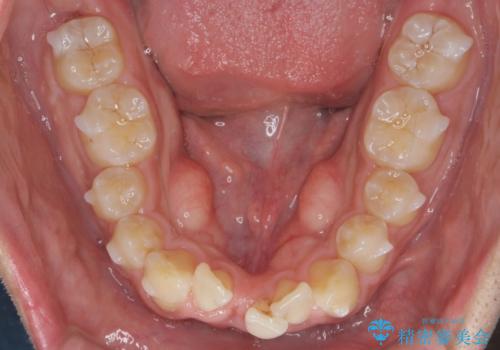

マウスピース矯正で前歯の角度、ガタガタをきれいに

- 突き出た前歯の角度、歯ブラシのしづらい前歯のがたつきの改善を希望され来院されました。

4本の小臼歯を抜きワイヤー矯正治療、下顎前歯を1本抜去しマウスピース治療のメリットデメリットを検討・相談し、より歯を抜く本数の少ないマウスピース矯正を行うこととなりました。

下顎の前歯は1本だけ抜去せざるをえませんでしたが、4本の小臼歯抜去とマルチブラケット矯正を回避することができ、治療結果・過程に満足いただくことができました。